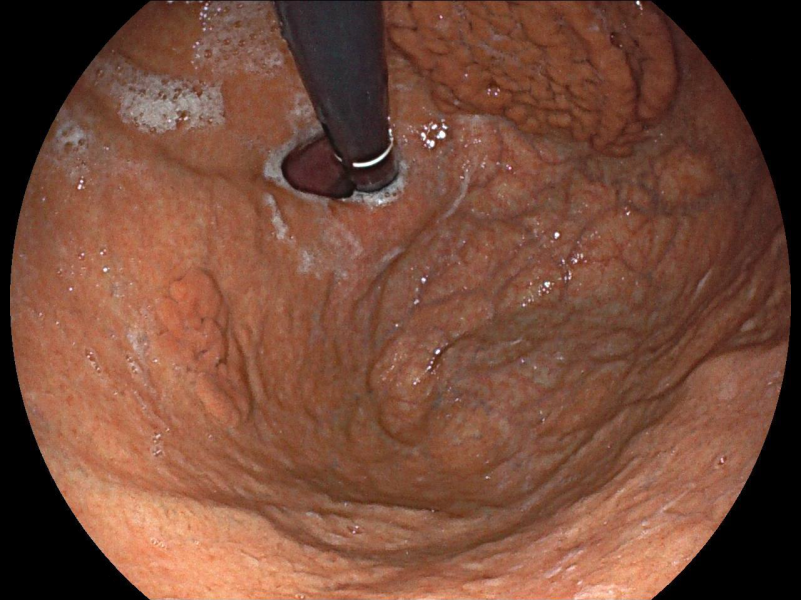

What is jejunal diverticula hiding?

Fotografia